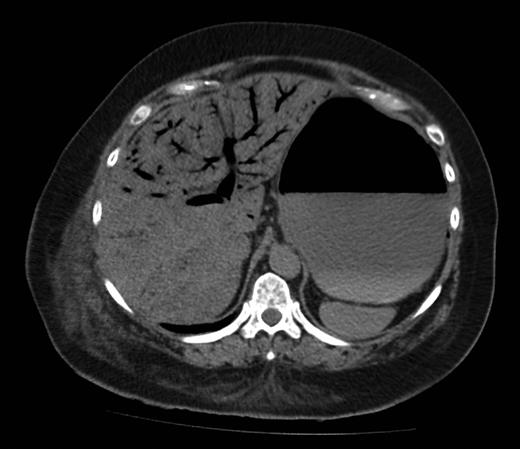

Figure 1 shows a remarkable amount of air in the hepatic portal venous system. Figure 2 demonstrates how the portal vein, splenic vein, superior mesenteric vein and its branches were all outlined with air. Figure 3 shows air within the wall of both small and large bowels. Overall, the radiological findings were suggestive of extensive bowel ischaemia.